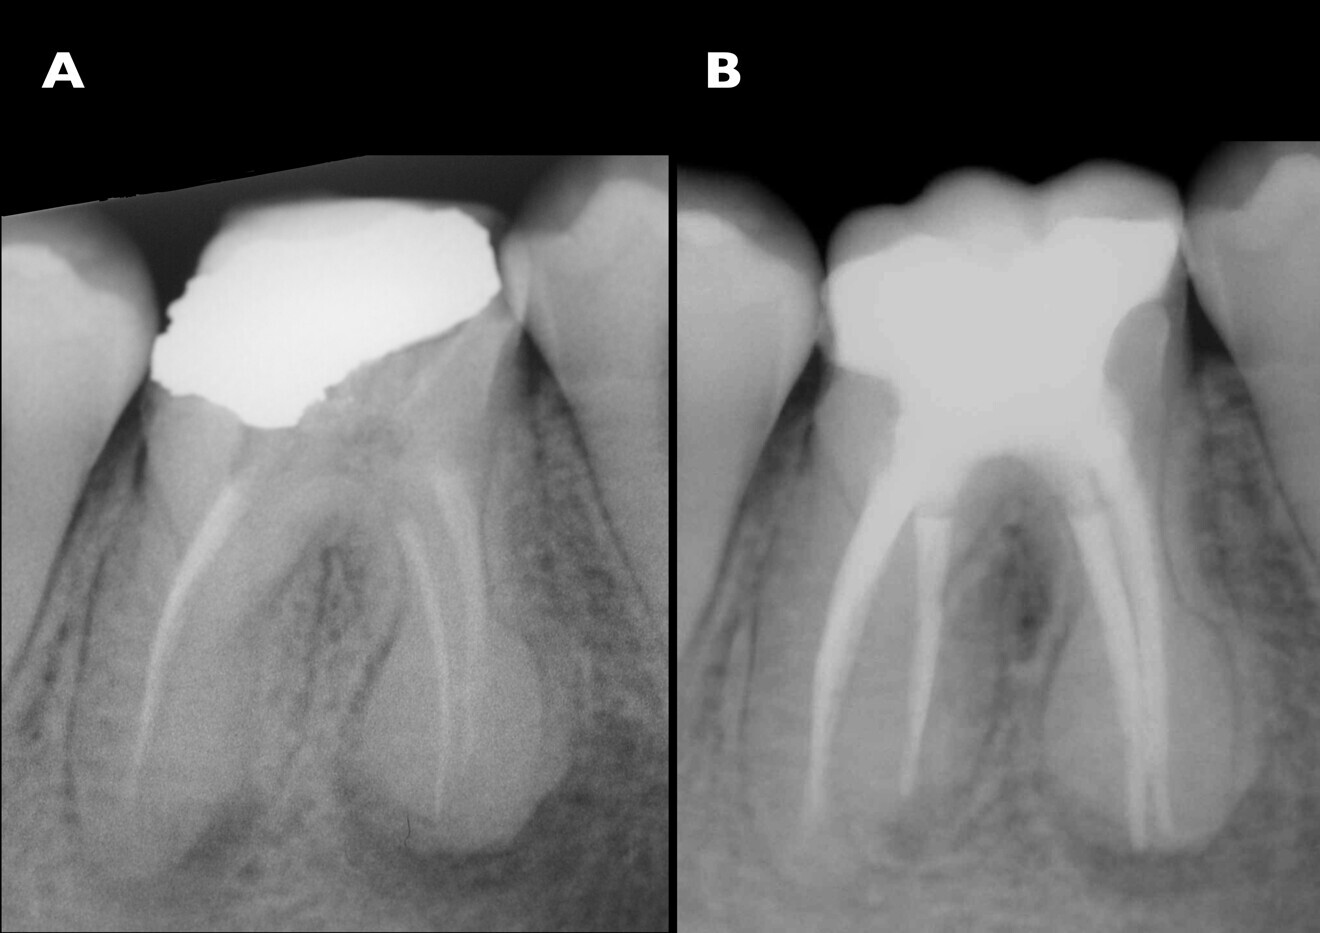

In the radiographic examination, the amalgam restoration showed open margins, especially on the mesial side (Fig. 1). The endodontic treatment was defective: the root canal preparation appeared to have been inadequate, and both the 3D seal and the working length were insufficient. A canal in the distal root seemed not to have undergone any endodontic treatment. Irregular root morphology compatible with hypercementosis was observed in the apical half of the roots of tooth #46, showing an increase of volume of a round shape. A widening of the periodontal space over almost all of its extent could also be observed. A significant apical lesion of the distal root and a smaller one of the mesial root were revealed as well.

The first step was the endodontic reintervention. After local anaesthesia, the operative field was isolated with a dental dam, and a dental dam clamp was placed around tooth #46. The old amalgam was removed, taking care to preserve sound tissue. Once the endodontic filling had been reached, remnants of amalgam and cement were carefully removed. The endodontic filling was removed with rotary instruments for canal shaping and retreatment (ProTaper Universal retreatment files, Dentsply Sirona). The coronal third was treated with the D1 file (30/0.09), the medium third with the D2 file (25/0.08) and the apical third with the D3 file (20/0.07). An entirely mechanical removal procedure was performed to avoid the use of endodontic solvents. The non-treated root canal in the distal root was located and manually prepared with size 15, 20 and 25 K-files. The same files were used for the radiographic check of the working length, which was measured with an apex locator (Fig. 2a).

ProTaper Next Conform Fit gutta-percha points (Dentsply Sirona), matched to the size of the canals prepared with ProTaper Next files, were inserted in each root canal and checked with an intra-oral radiograph (Fig. 2b). The root canals were then filled by means of a lateral condensation technique with cold gutta-percha and manual spreaders. Accessory gutta-percha points and an endodontic sealer (ADSEAL, Meta Biomed) were used as well.

Once completed, the gutta-percha points were cut manually with a hot instrument. After cleaning the dentine surface of the pulp chamber floor, a radiographic control was carried out (Fig. 3). The results were promising. The radiograph showed properly prepared, well-filled root canals, including the canal in the critical distal root. In all four root canals, the working and filling lengths were now well established.

Fig. 1: Radiograph of the pre-op situation showing insufcient endodontic treatment of tooth #46. Additionally, an amalgam coronal restoration with microleakage was detected. There were also apical lesions evident around both roots. Both neighbouring teeth had migrated towards tooth #46 and closed the interproximal spaces.

Fig. 2a: Radiographs of the endodontic treatment. Working length control (a).

Fig. 2b: Check of the extension of the Master gutta-percha points (b).

Fig. 3: Post-op results of the endodontic treatment. A proper 3D seal had been achieved. The working length and sealing had been corrected. The extra distal root canal had been found, treated and sealed.

Figs. 23a & b: Radiographs before (a) and after (b) treatment, showing dramatic differences. The endodontic treatment had been corrected and the restoration was well adapted and shaped. The interproximal relationships had been re-established through the anatomy of the endocrown. There were no gaps between the restoration and the endodontic filling. The sealing of the endodontic treatment was complete and tight.

Regarding the endodontic retreatment, the preparation and seal of the root canals were appropriate, a suitable 3D seal was achieved and the working length was corrected. Also, the previously untreated root canal in the distal root was properly prepared and sealed (Fig. 23).